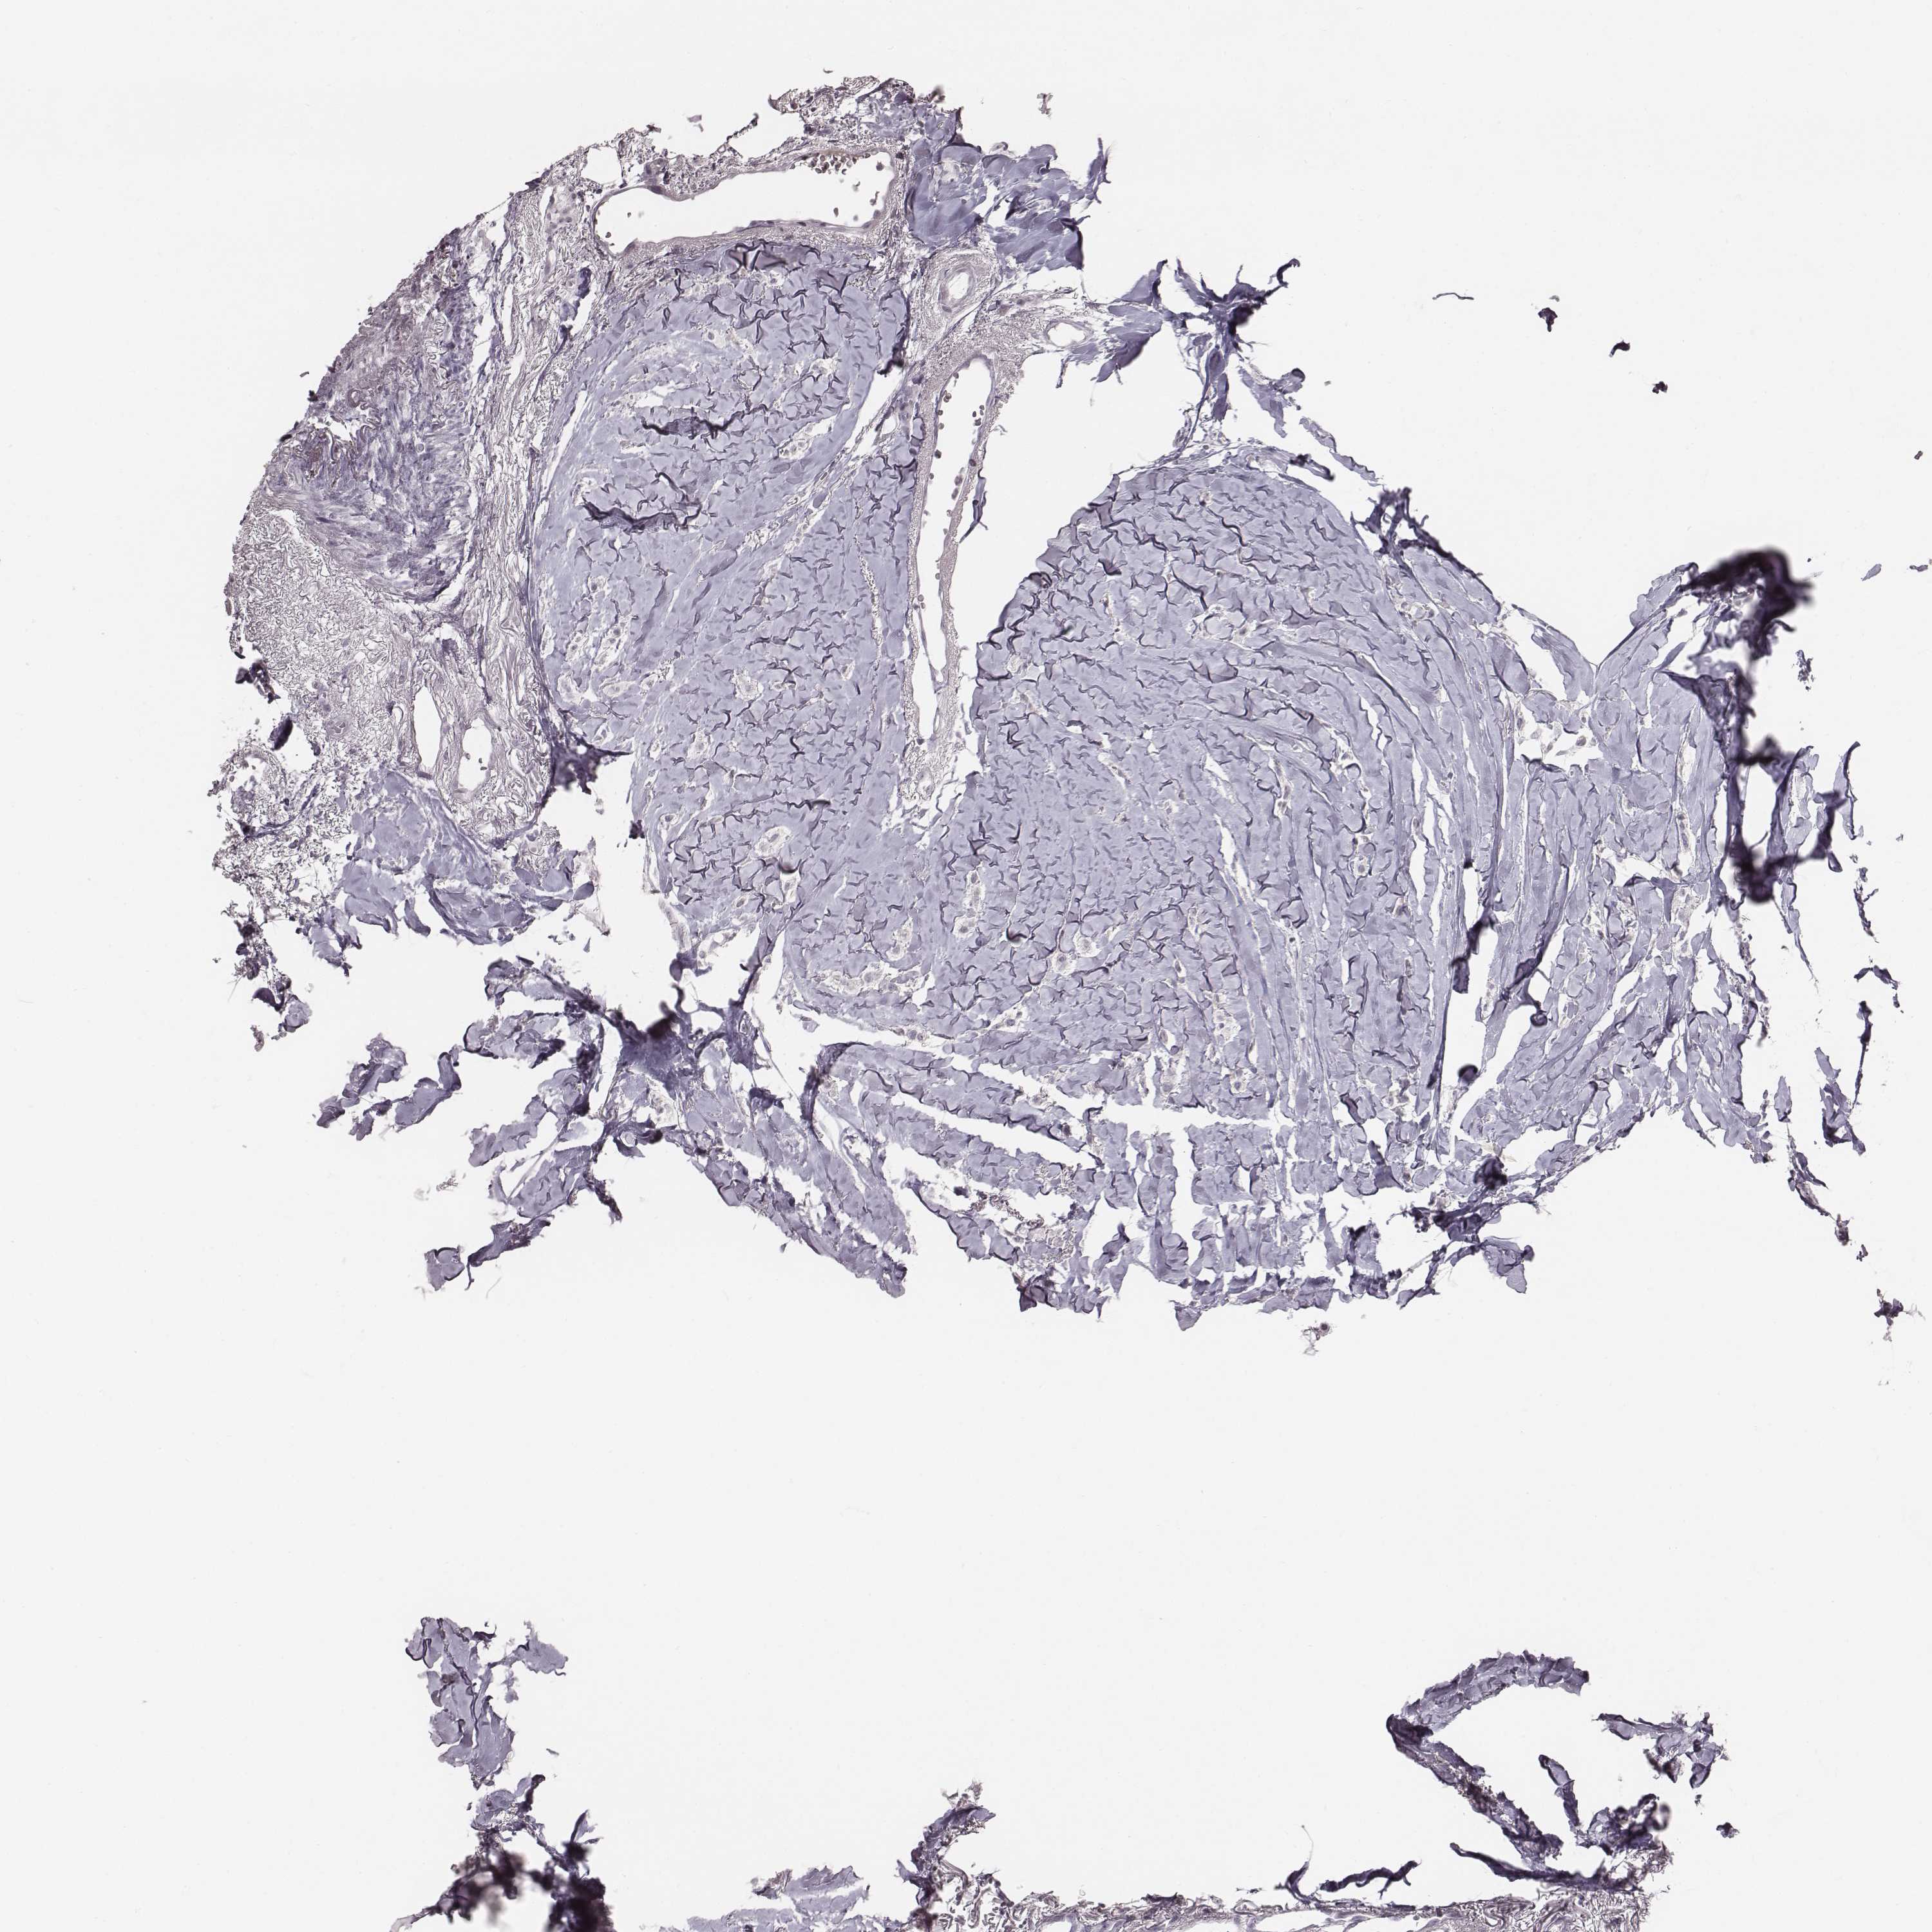

Breast cancer

Human cancer